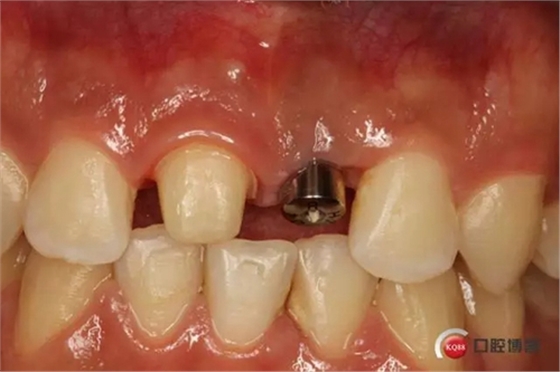

種植后修復,我們要把握每一個細節(jié),比色,轉(zhuǎn)移桿的就位,我們必須把臨床做好,技工師傅才會給我們做出好的修復體,減少一些不必要的失誤,首先術前的檢查是必要一步 ,再是器械的準備使我們臨床操作有條不紊,術前拍照,o-bite取咬合記錄,消毒修復術區(qū),旋出愈合基臺,生理鹽水沖洗袖口,拍照袖口,安放合適轉(zhuǎn)移桿,拍X線見轉(zhuǎn)移桿就為良好,硅橡膠取模,術后旋回愈合基臺,拍照比色。

藻酸鹽對頜取模,超硬石膏灌注。發(fā)加工廠,與技工溝通注意事項,等修復體做好后,檢查模型。是否就位,是否密合,預約患者復診戴牙,消毒修復區(qū),旋出愈合基臺,定位器指導安放修復基臺,試戴冠,調(diào)磨鄰接及 咬合至合適,拋光,患者滿意,加力扳手加力至30N,拍X片見就位良好,特芙蓉及暫封膏封中央螺絲孔,聚羧酸鋅粘固劑粘固,或是樹脂水門汀粘固,清理多余粘結(jié)劑,光固化樹脂封螺絲孔,拋光。術后注意隨訪。